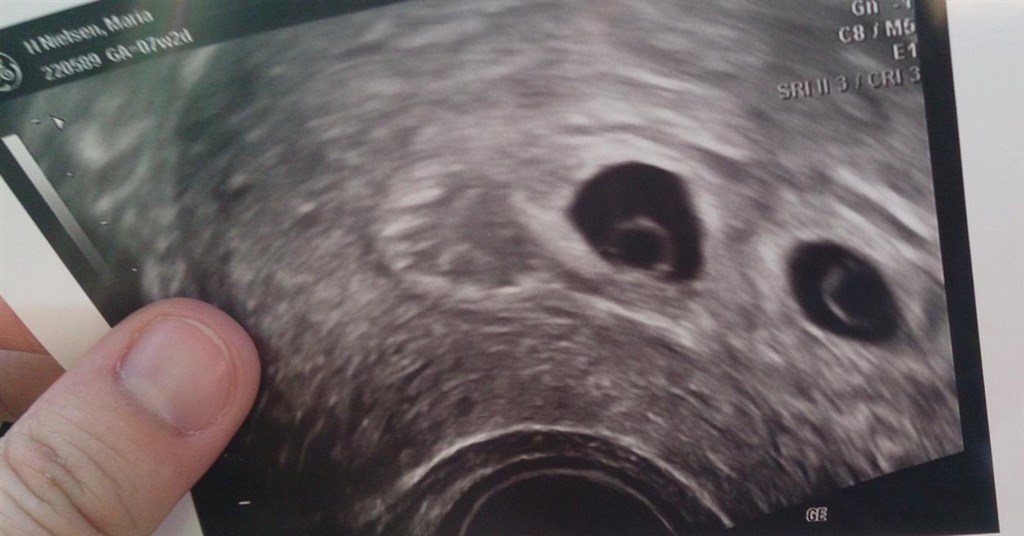

Prøv lige at se mit billede..

Fra 7+1-2

Hun sagde hun ikke rigtig kunne se noget..

Men når jeg ser på dit billede fra 7+1, så er der stadig lidt håb endnu.